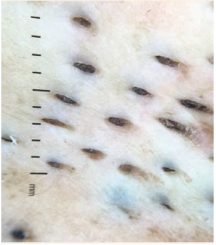

Paciente femenina de 45 años, con antece-dentes crónico-degenerativos de: hipertensión arterial sistémica, dislipidemia mixta y anemia ferropénica en tratamiento. Acudió a consulta con una dermatosis localizada en el tronco, unilateral, dispuesta linealmente, que afectaba la línea axilar media y la región mamaria derecha. Sobresalía una placa de 4 x 1 cm, conformada por comedones abiertos (Figuras 1y2). El padecimiento se inició desde que era niña y se refirió asintomática, sin aumento de la dermatosis. En la dermoscopia se observaron tapones de queratina color negro de 3 mm de diámetro (Figura 3). El reporte histopatológico de la biopsia incisional fue de: epidermis dis-cretamente acantósica, con estrato córneo en red de canasta; con múltiples folículos pilosos dilatados, con tapones córneos, algunos con

En la dermoscopia se observan tapones de que-ratina bien delimitados, color negro, de 1-3 mm de diámetro, áreas homogéneas con tapones hi-perqueratósicos con distintos tonos de marrón,13 que es la misma imagen que tenía la paciente de nuestro reporte.